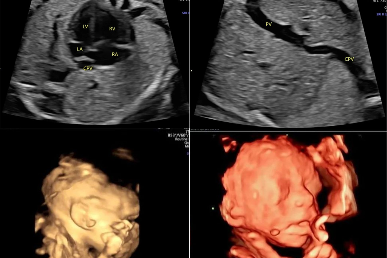

疑难病例 | 产前超声诊断中的异常病例